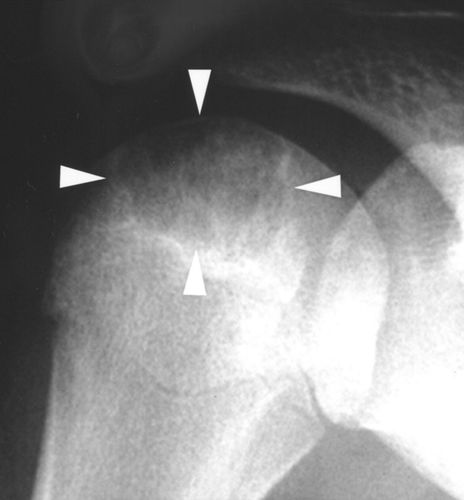

软骨母细胞瘤,通常存在于长骨的骨骺(或隆起)(图2A)。它们往往很小(<4 cm),大多数(≈75%)表现出硬化边界[2,3]。在三分之一的患者的X光片上可见钙化基质[4]。当软骨母细胞瘤延伸到干骺端并且缺乏硬化边缘和钙化时,它们可以模仿巨细胞瘤(图2B)。与巨细胞瘤不同,软骨母细胞瘤存在于较年轻的年龄组,通常在骨骼成熟之前。软骨母细胞瘤很少将肿瘤扩展到软组织中。

图2A-软骨母细胞瘤。16岁女孩的射线片显示典型的肱骨近端骨骺的软骨母细胞瘤(箭头)。

图2B-软骨母细胞瘤。16岁男孩胫骨近端干骺端和骨骺(箭头)有非硬化边缘, X线外观很像巨细胞瘤,但是由于年龄较小,不能明确诊断为典型的骨巨细胞瘤。